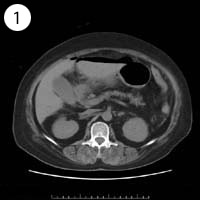

57歳 女性

異常のある4枚組は?

単純CT